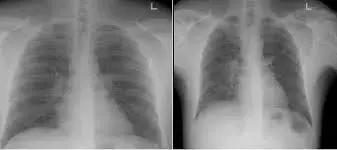

他建议,如果你咳嗽超过4周,那就要做X光扫描,排除肺炎或其他流感可能性。

图源:SGH